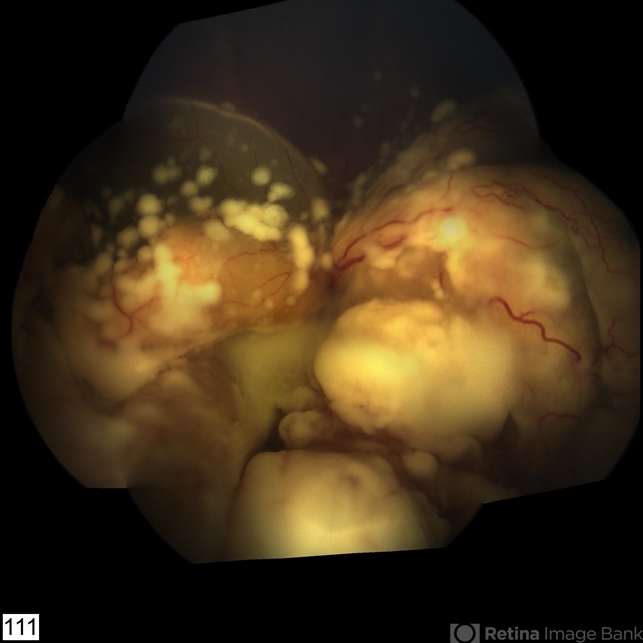

- tumor, tumor seeding

- Imaging device

- RETCAM III 130 degree lens montage

- 2-year-old boy with stage D+ retinoblastoma of the right eye.